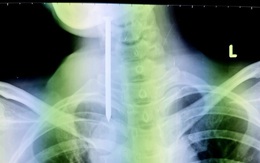

Phẫu thuật lấy đinh dài 8cm do bệnh nhân rối loạn tâm thần tự nuốt

TTO - Một bệnh nhân tâm thần không ổn định, tự nuốt cây đinh khoảng 8cm, sau đó ho khạc ra máu, được gia đình đưa vào cấp cứu tại Bệnh viện Đa khoa Cần Thơ.